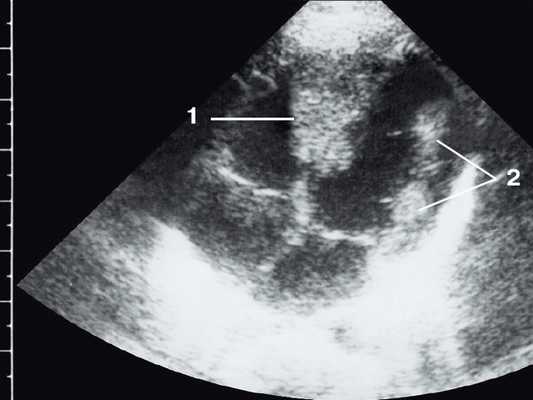

Широкое внедрение в практику ультразвуковой диагностики позволило перейти от аутопсийной статистики к прижизненному выявлению. Эхокардиография - первый метод выявления рабдомиомы сердца и контроля состояния пациента в динамике. Учитывая очень большое число семейных случаев, необходимо обследование всех ближайших родственников, особенно при наличии у них пятен цвета кофе с молоком, депигментированных по типу шагреневой кожи, параунгвальных и параореолярных фибром, ранних миом матки, инфантильных спазмов, судорожных припадков и других признаков факоматозов. При семейных обследованиях рабдомиомы сердца могут выявляться у совершенно бессимптомных носителей (рис. 1, 2).

Рис. 2. Эхокардиограмма матери этого же ребенка. В межжелудочковой перегородке несколько эхоплотных образований (стрелки).

Рабдомиома сердца эхографически выглядят как достаточно четко очерченные образования. Чаще всего располагаются в миокарде левого желудочка, реже - в правом, еще реже - в предсердиях, кавоатриальных и атриовентрикулярных соединениях, эпикарде. Метастазирование не типично [8]. Наличие двух и более рабдомиом четко коррелирует с туберозным склерозом, одиночные рабдомиомы сердца такой связи, как правило, не имеют. По нашему опыту (18 пациентов), чем меньше объем новообразования, тем выше акустическая плотность, приближающаяся к эталонной эхоплотности (эндо-, эпи- и перикард). Эхоплотность больших рабдомиом практически не отличается от эхоплотности миокарда. В толще новообразования выявляются мелкие эхонегативные очажки (области некрозов) и эхопозитивные очажки (отложения кальция) (рис. 3).